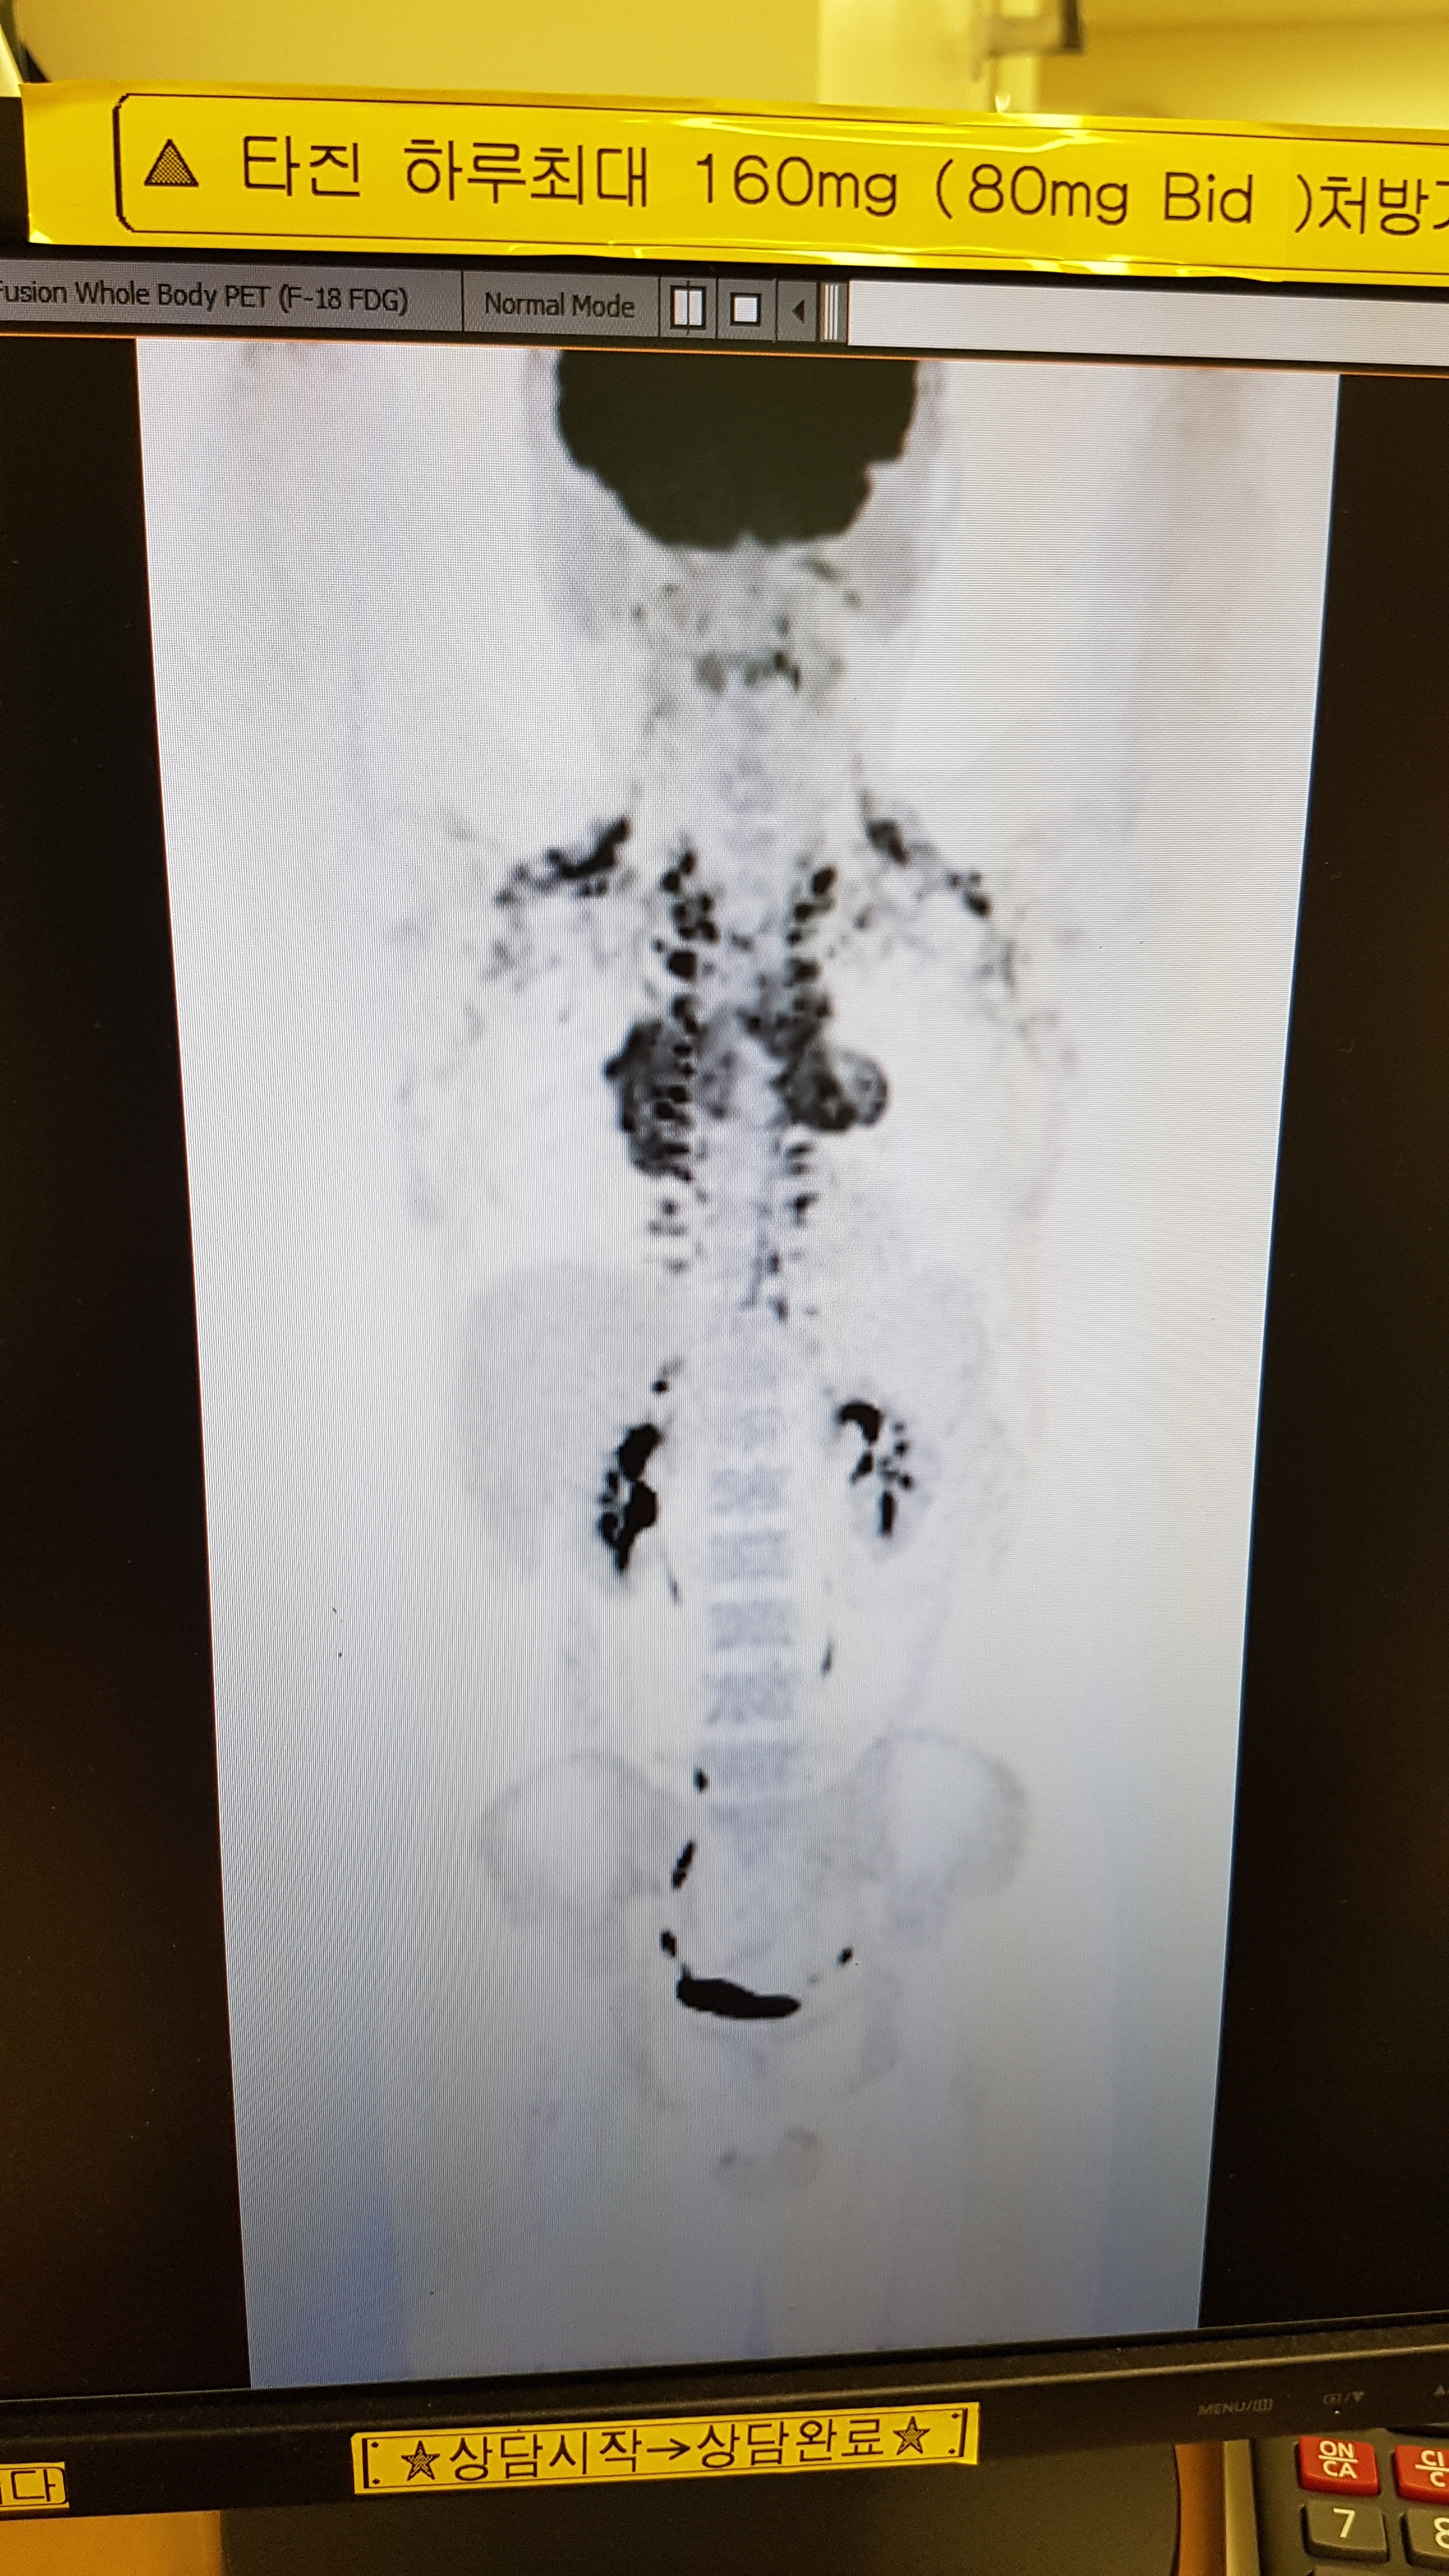

Ç÷¾×¾Ï, ¸²ÇÁÁ¾Àε¥ Áö±ÝÀº °¡½¿ÆÅÂÊ¿¡ Á¾¾ç¸¸ °ÅÀÇ ³²Àº»óȲ. ¹ß°ß ´ç½Ã CTÀε¥ ¾î±ú¶û ¸ö¿¡ ´Ù ÆÛÁ®ÀÖ´ø»óȲÀÌ¿¡¿ä

³ú»©°í °ÅÀÇ ´Ù ÆÛÁ®ÀÖ¾ú´ø°Å¶ó°í µé¾ú°í Ç÷¾×¾ÏÀº ÀÇ»ç½ÜµéÇÑÅ× ¹°¾îº¸´Ï ÆÛÁö´Â Á¤µµ°¡ »ó°ü¾øÀÌ Ä¡·á¹ýÀÌ °°´Ù°í ÇÏ´õ¶ó°í¿ä. Ç÷°üŸ°í Ÿ°í´Ù´Ï´Â°Å¶ó.. ÃÖ±Ù ¾¾Æ¼¿¡¼ °¡½¿Âʸ¸ ³²¾Ò¾ú´Âµ¥ Á¶¸¸°£ Ä¡·á ´Ù ³¡³ª°í Á¤¸®Çؼ ±Û¿Ã¸®°Ú½À´Ï´Ù. ´Ùµé °¨»çÇÕ´Ï´Ù

¤¤ ¾Ï¼¼Æ÷°¡ ÇǸ¦ Ÿ°í ¸ö ±¸¼®±¸¼®¿¡ ÆÛÁø°Å °°¾Æ¿ä